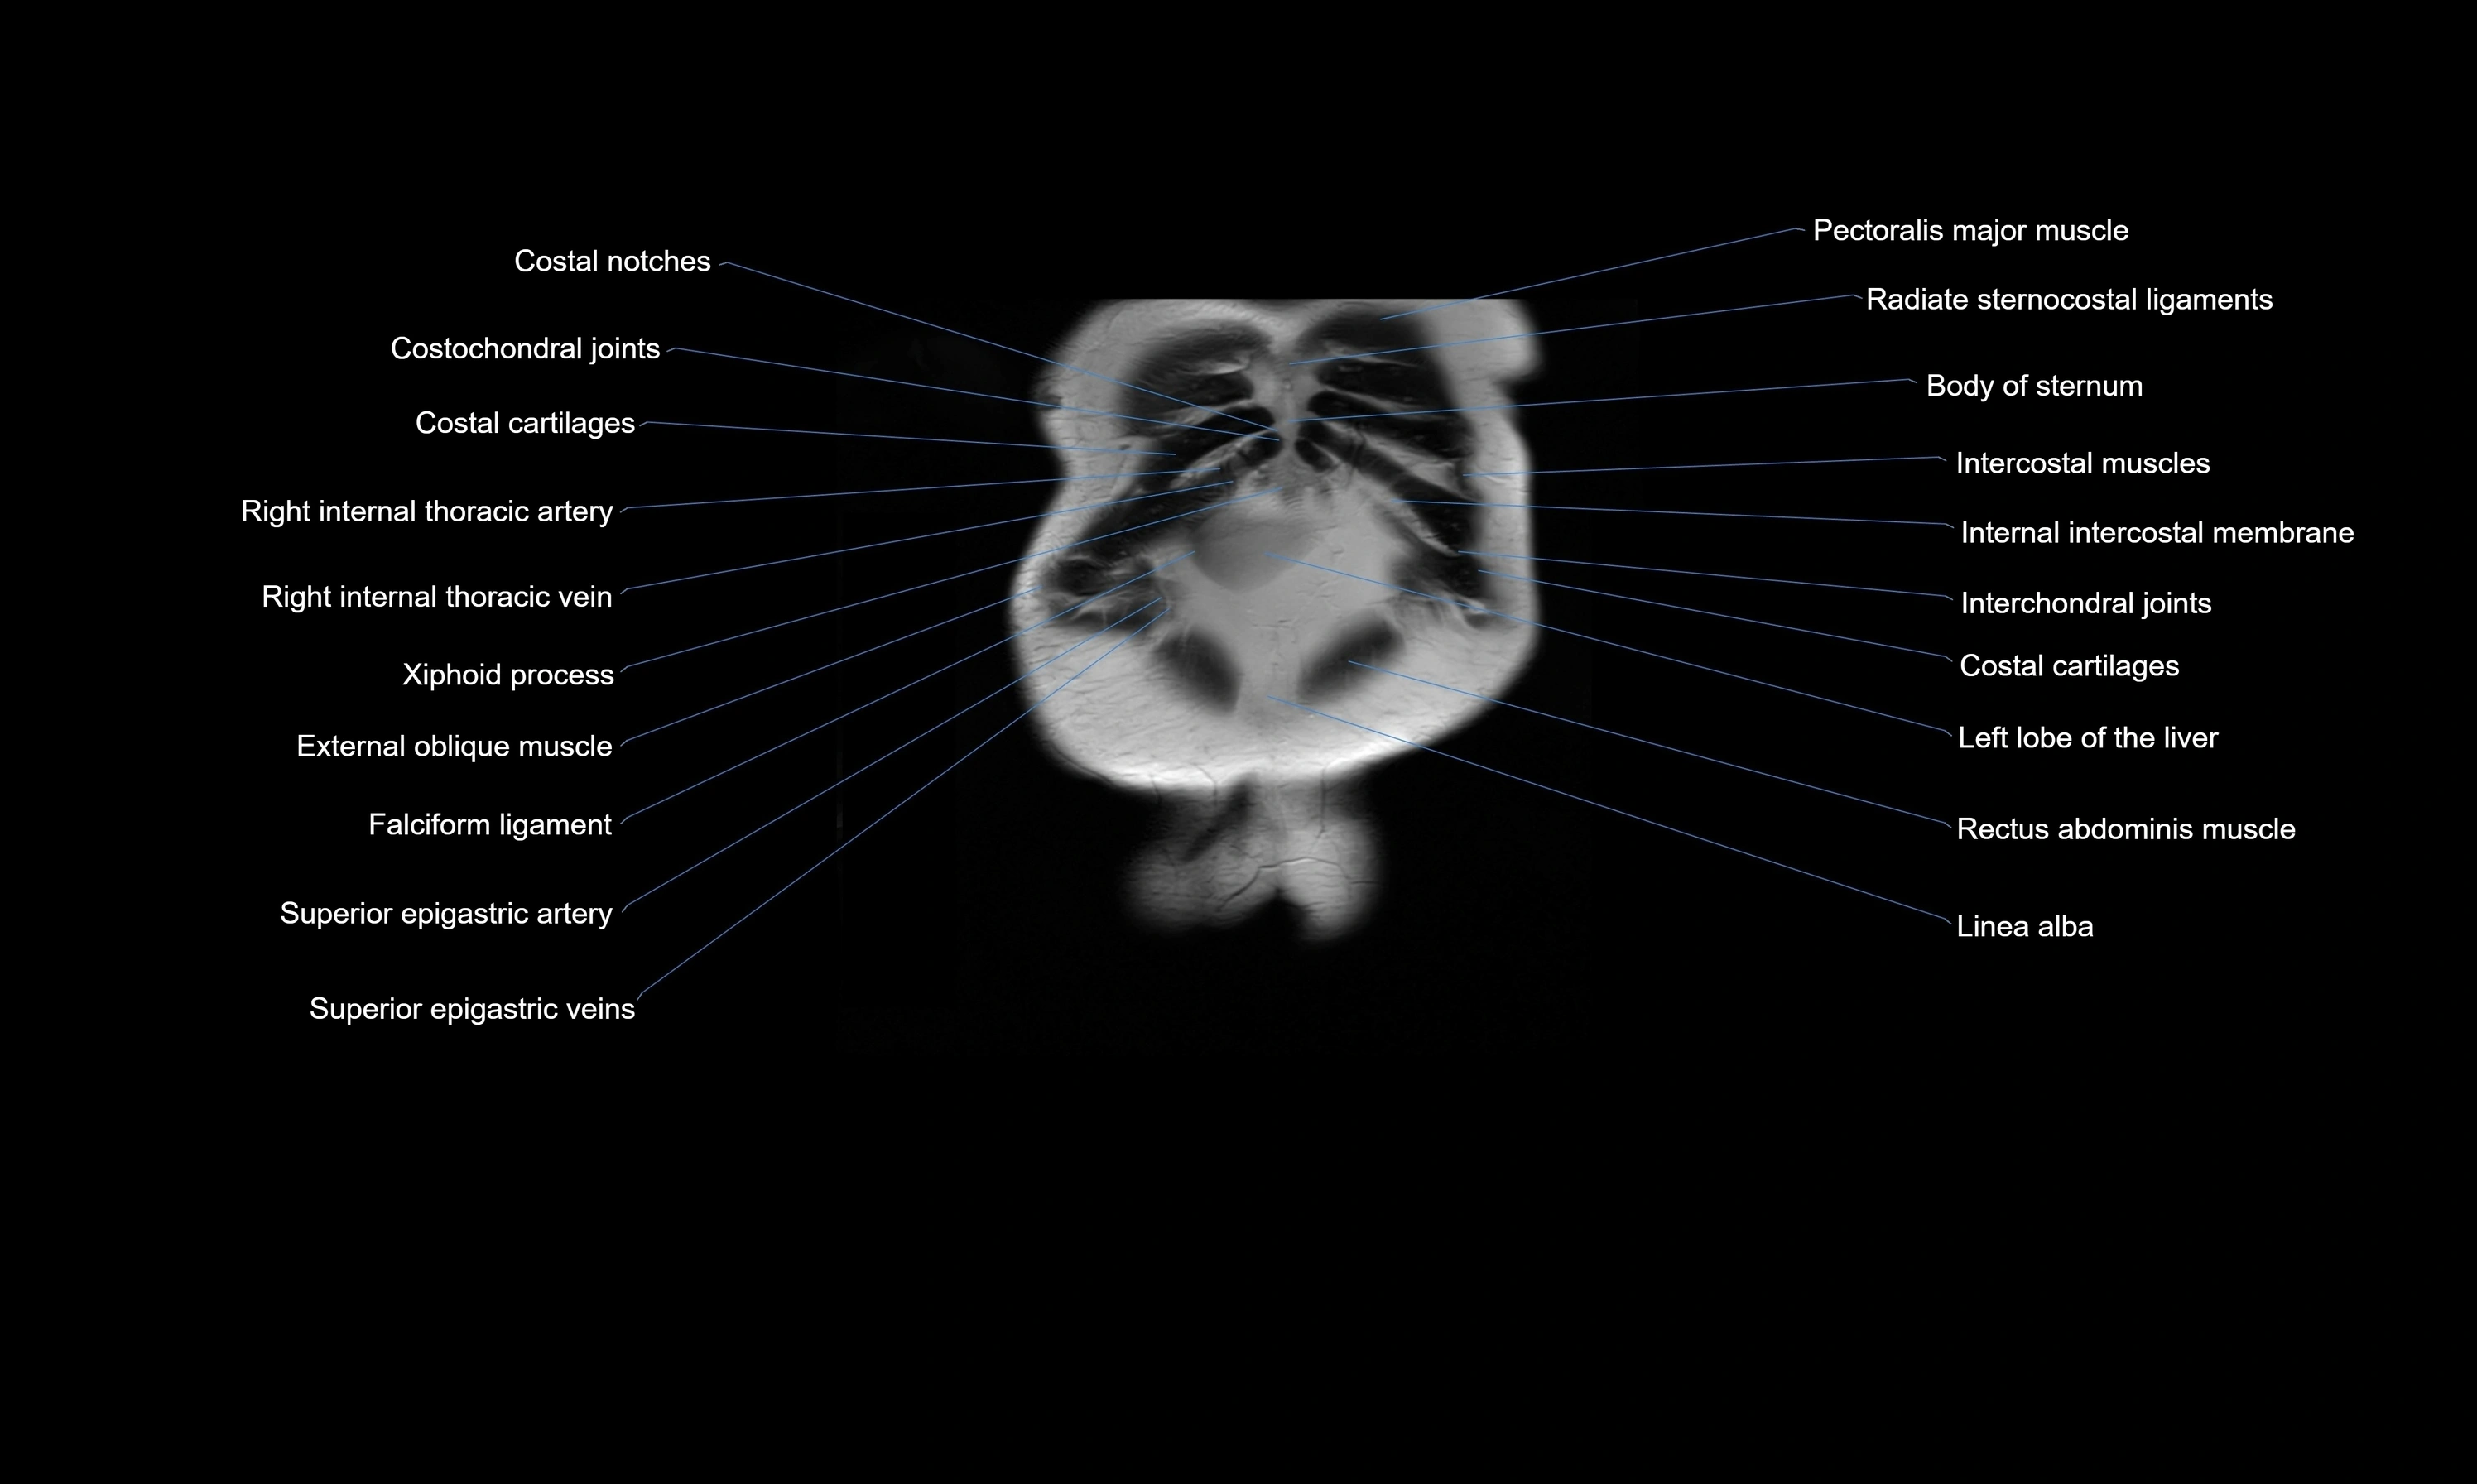

MRI images